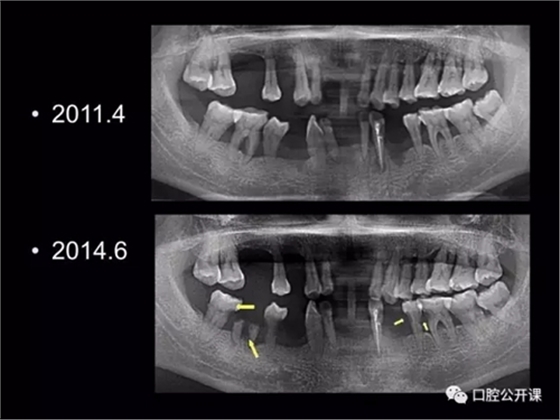

楊淑銀醫(yī)師用他的一例侵襲性牙周炎五年臨床病例追蹤來(lái)縮影一個(gè)青年牙周醫(yī)師的成長(zhǎng)之路,帶我們一起探索看似平凡枯燥的牙周基礎(chǔ)治療到底有怎樣的重要性?